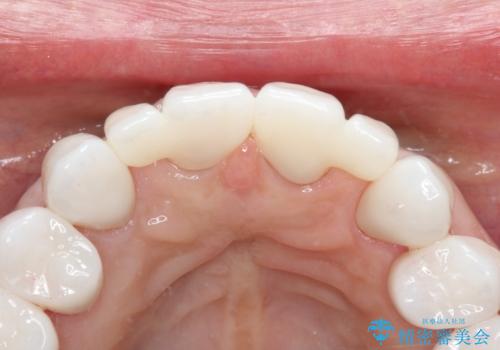

【オールセラミッククラウン】前歯を綺麗にしたい。

- 前歯の被せもののやりかえを主訴に来院されました。

前歯の歯茎から膿も出ていたため、歯内治療を行なったのち修復を行なっております。

根管治療および外科的歯内療法を行なってから被せものの処置を行なっております。